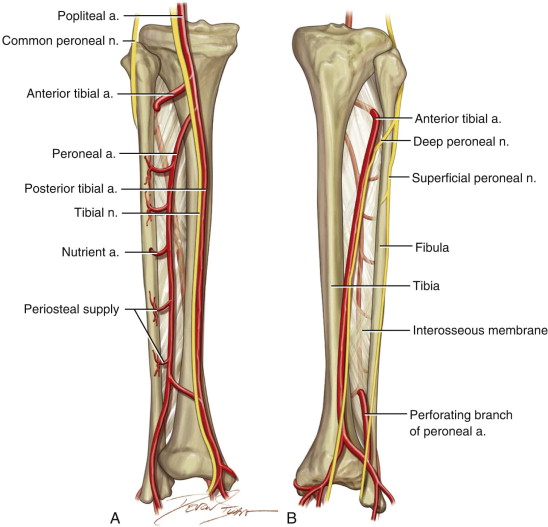

Схема на тибия и фубула

Графично изображение на малкия пищял - фибула. Това представлява дълга и сравнително здрава кост, която няма много голяма функция в организма. При премахване на фибулата и правилно протичане на оздравителния процес първоначално има силна болка и различно изразено двигателно нарушение, но в крайна сметка не остава никакъв функционален дефицит. Освен това като форма и големина фибуларният трансплантат силно наподобява долната челюст, поради което е много удобен за реконструкции на липсваща мандибула. При пациент със среден ръст е възможно да се вземе костна тъкан с дължина 22 - 24 сантиметра, което в повечето случаи е достатъчно за възстановяването на масивни костни дефекти. Нерядко е възможно да се изгради дори и цяла долна челюст след тотална резекция; двете малеолусни ставни главички могат да се използват и за реконструкция на темпоромандибуларната става. В областта на горната челюст фибуларните трансплантати се използват по-рядко, въпреки че срязването на малкия пищял на няколко сегмента и нагъването им осигурява възможност за максиларна реконструкция.

Схема на кръвоснабдяването на двата пищяла - тибия и фибула. Принципно като основен хранещ съд за фибуларното ламбо се използва задната тибиална артерия - a. tibialis posterior. Тя се изчерпва на нивото на глезена и въпреки инсуфициентното кръвоснабдяване на крака нейното лигиране и премахване заедно с повдигнатото ламбо не създава трофични проблеми. Доста по-различни е положението с предната тибиална артерия - a. tibialis anterior. Тя трябва да бъде съхранена на всяка цена, защото е основен хранещ съд за ходилото. При наличието на съвременни компютърни томографи с големи диагностични възможности е задължително да се направи предоперативна контрастна томография. Тя открива различни съдови вариации, които изобщо не са редки и по този начин се избягват усложненията от нарушеното кръвоснабдяване.